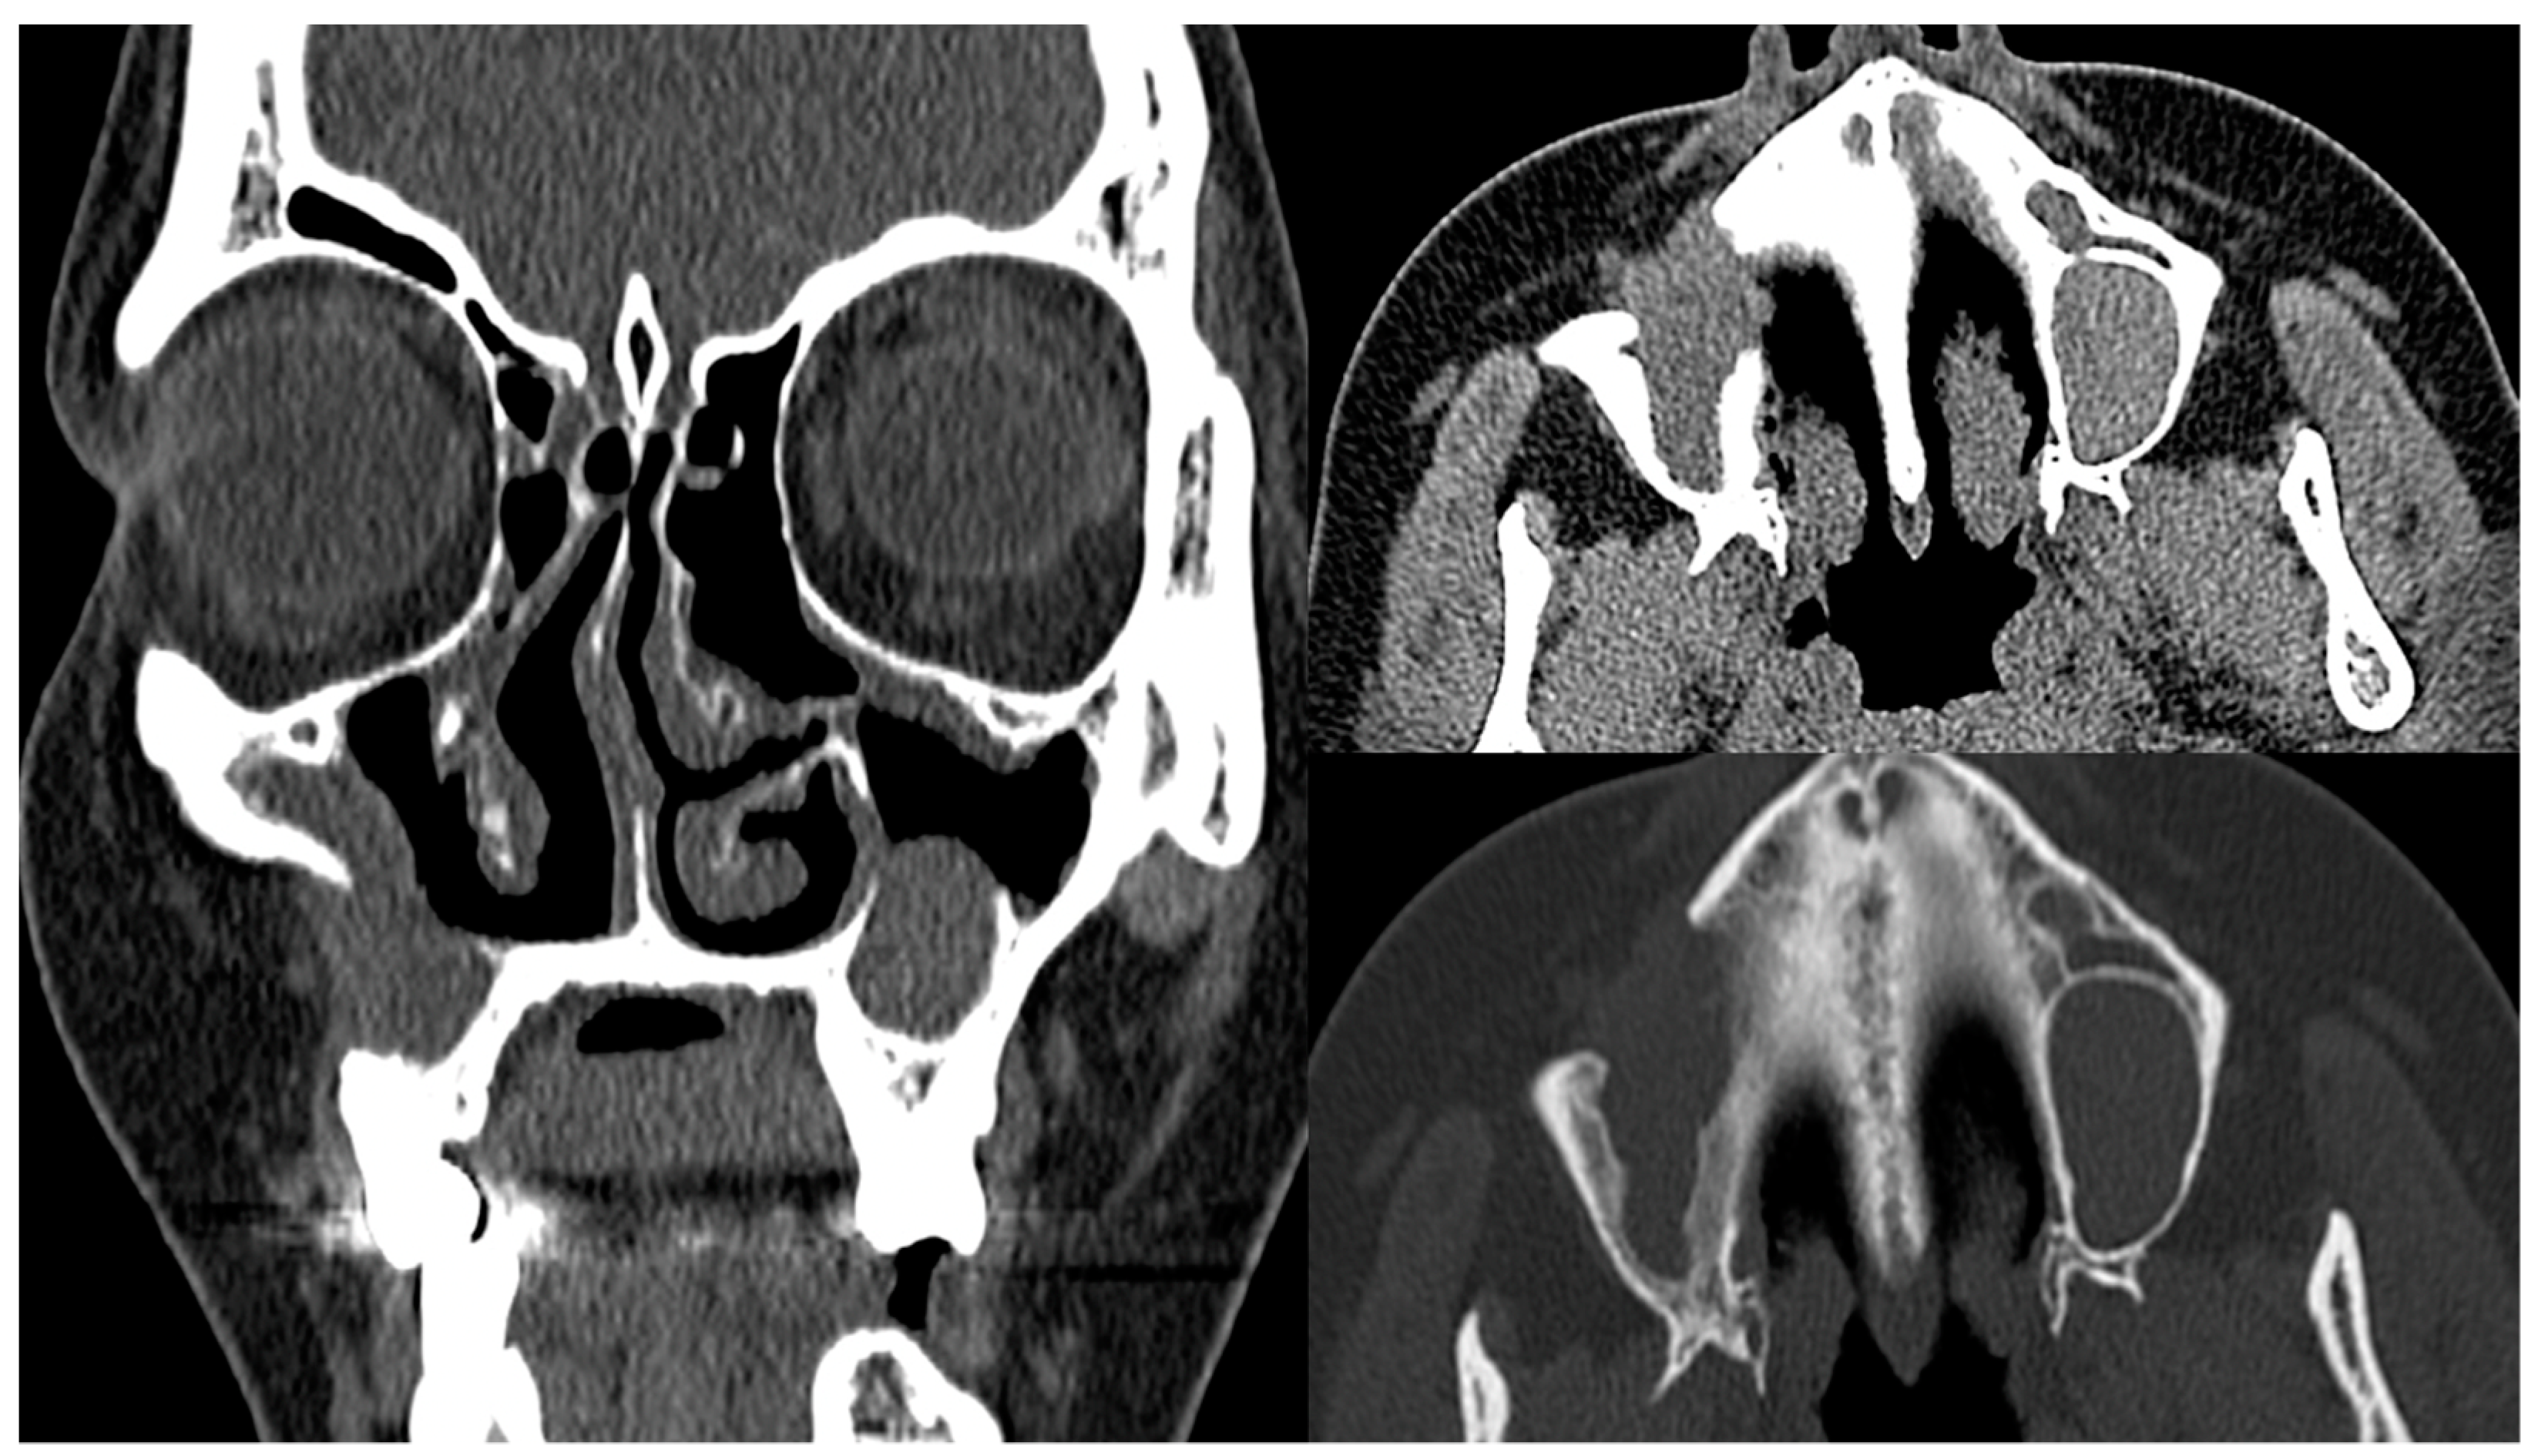

- Fujita, A.; Sakai, O.; Chapman, M.N.; Sugimoto, H. IgG4-related disease of the head and neck: CT and MR imaging manifestations. Radiographics 2012, 32, 1945–1958. [Google Scholar] [CrossRef]